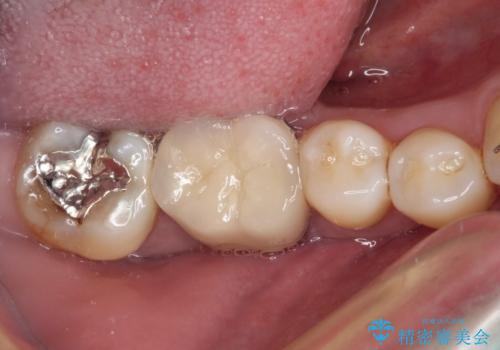

捻れた前歯と銀歯のブリッジを治したい ワイヤー矯正とオールセラミックブリッジ